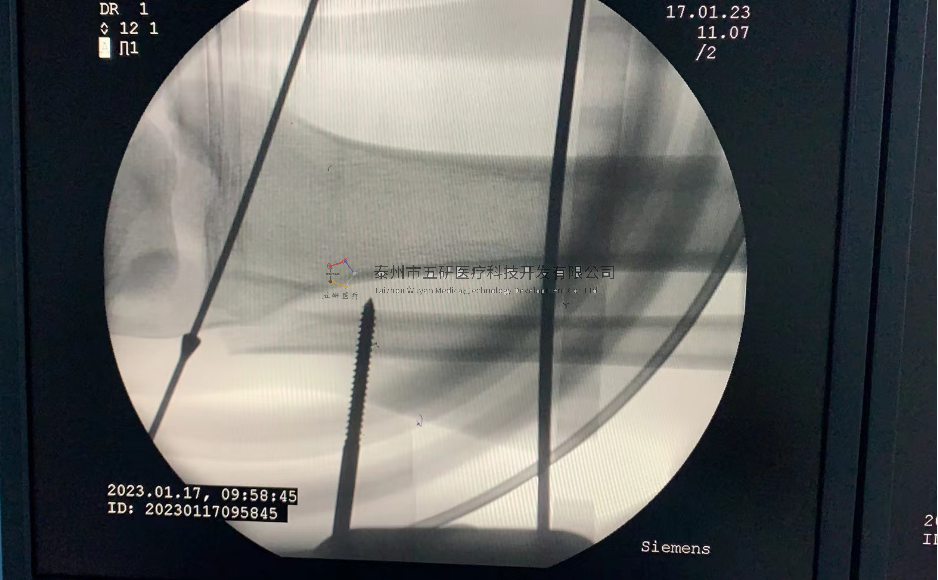

本病例腕架骨折。術(shù)前正側(cè)位片:右橈骨遠(yuǎn)端骨折。

采用常規(guī)方法固定,自掌骨尺側(cè),約基底稍偏遠(yuǎn)處穿入螺紋針。

1.webp.jpg